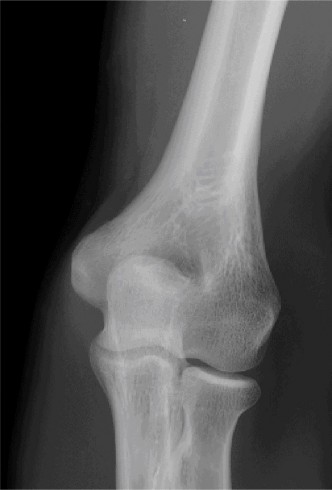

Examination reveals deformity about the elbow with no open lesions or skin tenting. He has a palpable radial and ulnar pulse and is neurologically intact. His images are shown (Figs. 2–85 to 2–88).

Figure 2–85

Figure 2–86

Figure 2–87

Figure 2–88

What is the diagnosis and direction of displacement?

- Monteggia fracture dislocation, posterolateral displacement of the forearm about the humerus

- Simple elbow dislocation, posterolateral displacement of the forearm about the humerus

- Transolecranon complex elbow dislocation

- Simple elbow dislocation, posteromedial displacement of the forearm about the humerus

Discussion

The correct answer is (B). This is the most common type of elbow dislocation, and often does not cause any osseous injury. Posterolateral and posteromedial dislocation account for approximately 90% of dislocations. Adequate pre- and postreduction films are necessary to evaluate for fracture, which would change the classification to a complex injury.